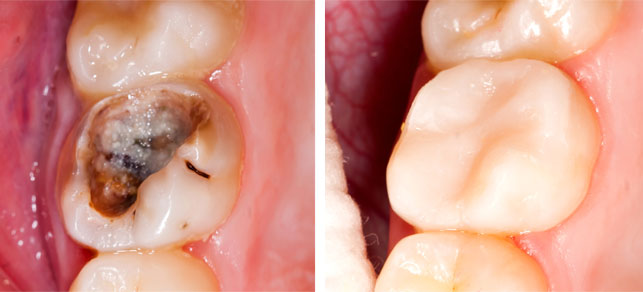

RESTORATION

When your tooth has a cavity, you will need a good filling. At 5 star dental, the cavity will be removed easily and comfortably. Also, we provide different filling materials with different colors to provide the optimal result and for your satisfaction.

CROWN AND BRIDGE

When a simple filling cannot solve the problem, then you will need a crown or bridge. We will prep and deliver the crown or bridge to restore the functionality of your tooth by carefully selecting its size, shape, material and color.